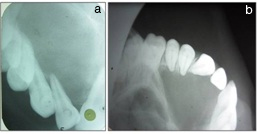

A swelling was seen on the bucco-gingival area extending upto the palatal surface in relation with 21 which was approximately 0.5x0.5cm, oval in shape having colour same as that of adjacent mucosa [Table/Fig-3]. On the basis of clinical evaluation we arrived to a provisional diagnosis of Radicular cyst with 21. Several investigations were carried out in order to obtain a confirmatory diagnosis namely, IOPA which was suggestive of a well-defined radiolucent line involving 21,22,23,24,25 appearing radiolucent in nature & an occlusal radiograph suggestive of the same [Table/Fig-4a,b].

Radiographic view showing site of lesion in an IOPA and occlusal view which appears as radiolucent area